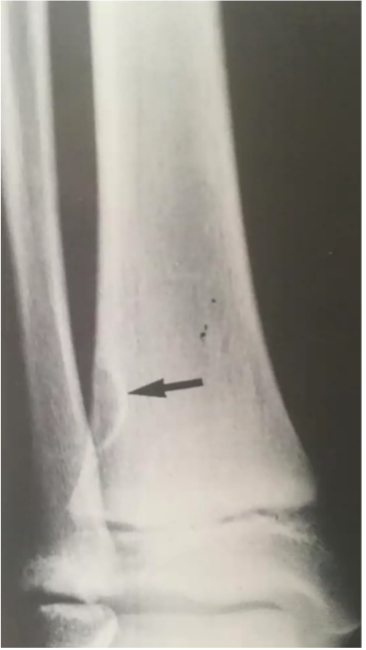

Fibrome non-ossifiant : bénin et ASX

- C’est une plus grosse version du défaut fibreux cortical

- 8-20 ans

- 2-7 cm, ovoid, excentré, bien défini

Défaut fibreux cortical : bénin et ASX pas de C-I à l’ajtm

- Distal tibia ou os long, dans la métaphyse

- Tissus fibreux remplace le cortex

- Bien défini/bien cirsconscrit/géographique